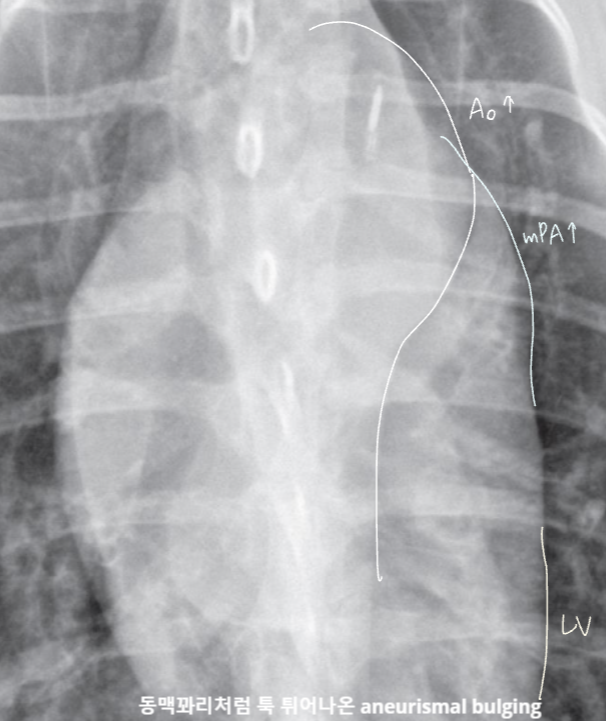

Patent Ductus Arteriosus

| PDA |

|---|

| ํ์๋์์ด์ผ ํ ๋๋งฅ๊ด์ด ์ด๋ ค ์๋ ์ํ |

| Radiographic sign - [3 bumps] Ao bulging, mPA bulging, LA&LV enlargement (Ao์ mPA๊ฐ ๊ฐ์ด ์ปค์ง๋ ๊ฑด PDA๋ฐ์.) |

![]() ![]() |